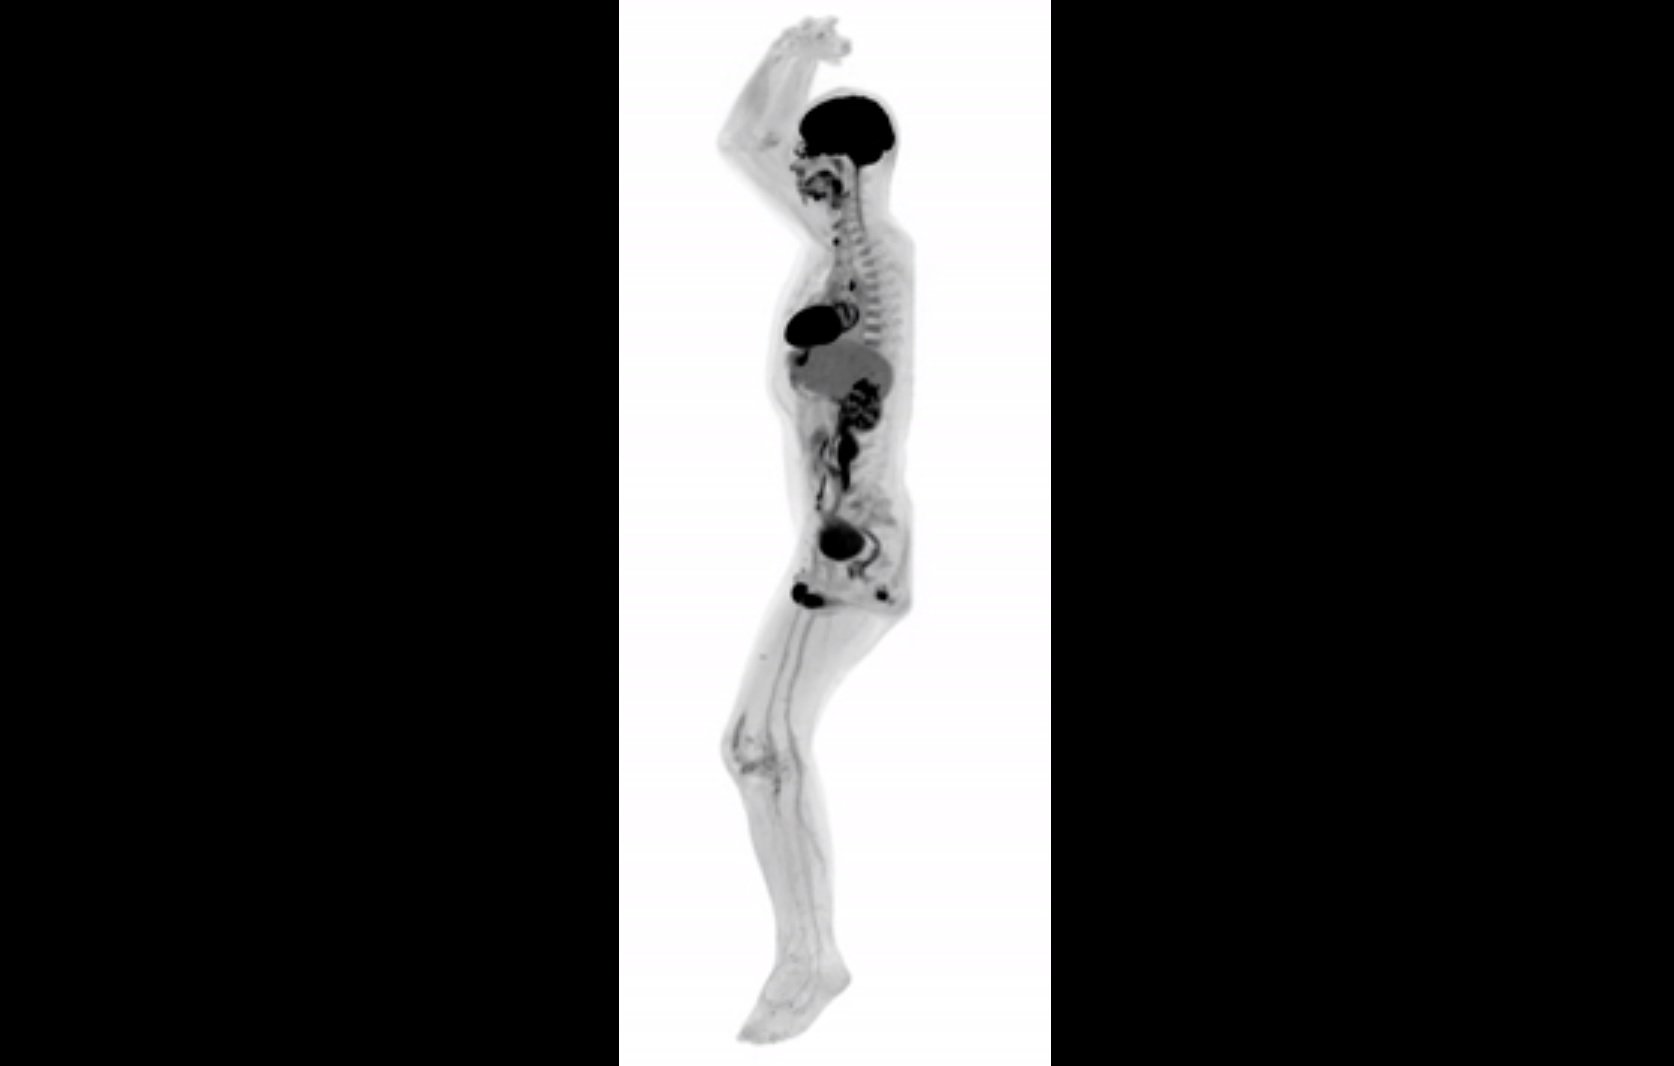

United Imaging Healthcare (UIH) EXPLORER, , . , . - EurekAlert!

EXPLORER - () . , , , , .